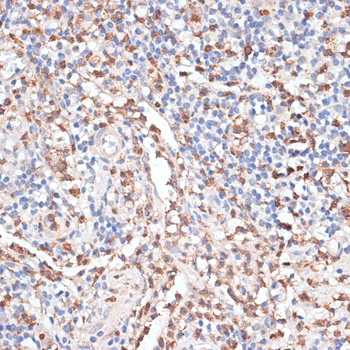

Immunohistochemistry of paraffin-embedded human tonsil using CTSG at dilution of 1:100 (40x lens).

Immunohistochemistry of paraffin-embedded human appendix using CTSG at dilution of 1:100 (40x lens).

Immunohistochemistry of paraffin-embedded human uterine cancer using CTSG at dilution of 1:100 (40x lens).

Immunohistochemistry of paraffin-embedded mouse spleen using CTSG at dilution of 1:100 (40x lens).